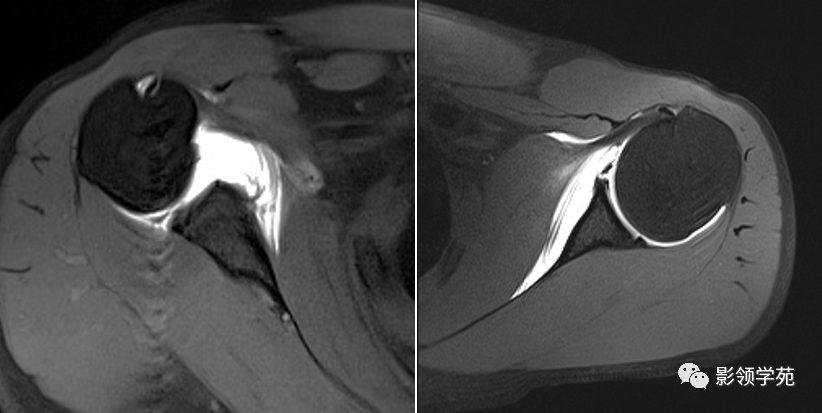

冈上肌撕裂

图3 巨大肩袖损伤的核磁,可以看到冈上肌肌腱撕裂,回缩,原来冈上肌

核磁斜冠位示冈上肌冈下肌撕裂,其中冈上肌断端回缩至肩盂水平,术前